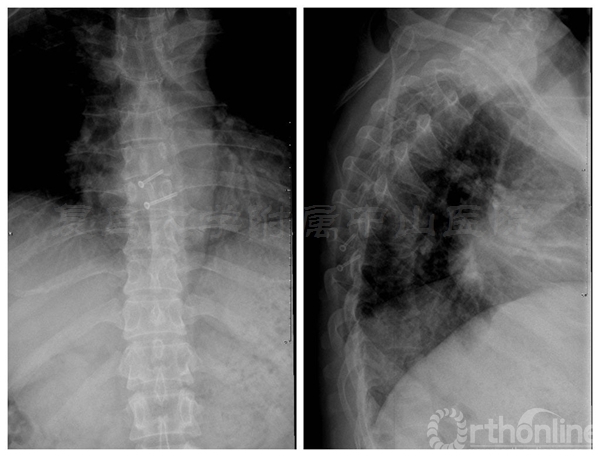

术前胸椎正侧位X线:未见明显骨质异常

术中椎板截骨行肿瘤切除后,椎板回植术,回植椎板采用空心螺钉固定

术后肌力恢复至4+级,无脑脊液漏,X线片及CT平扫显示椎板回植位置满意,空心钉固定牢靠。术后病理诊断为脊膜瘤伴细胞丰富